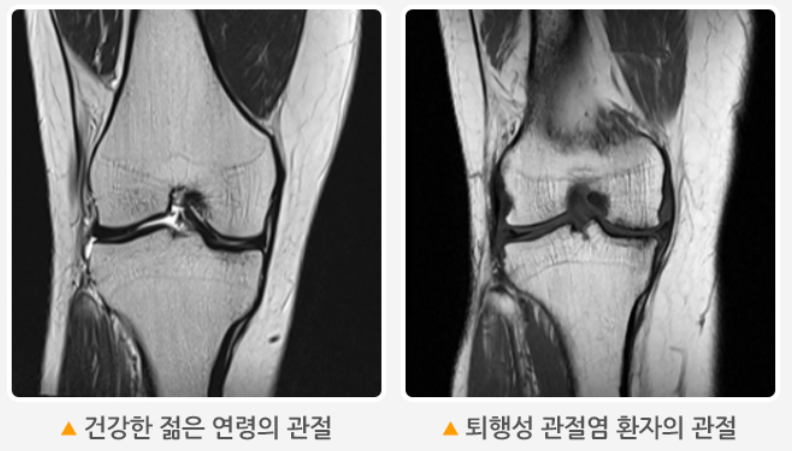

잘못된 걸음걸이, 장시간 앉은 자세, 운동 부족, 과체중 등이 무릎에 부담을 줄 수 있습니다. 특히 무릎 뼈와 뼈 사이의 연골이 닳거나, 무릎 주변 근육이 약화되면 통증이 더 심해질 수 있죠.